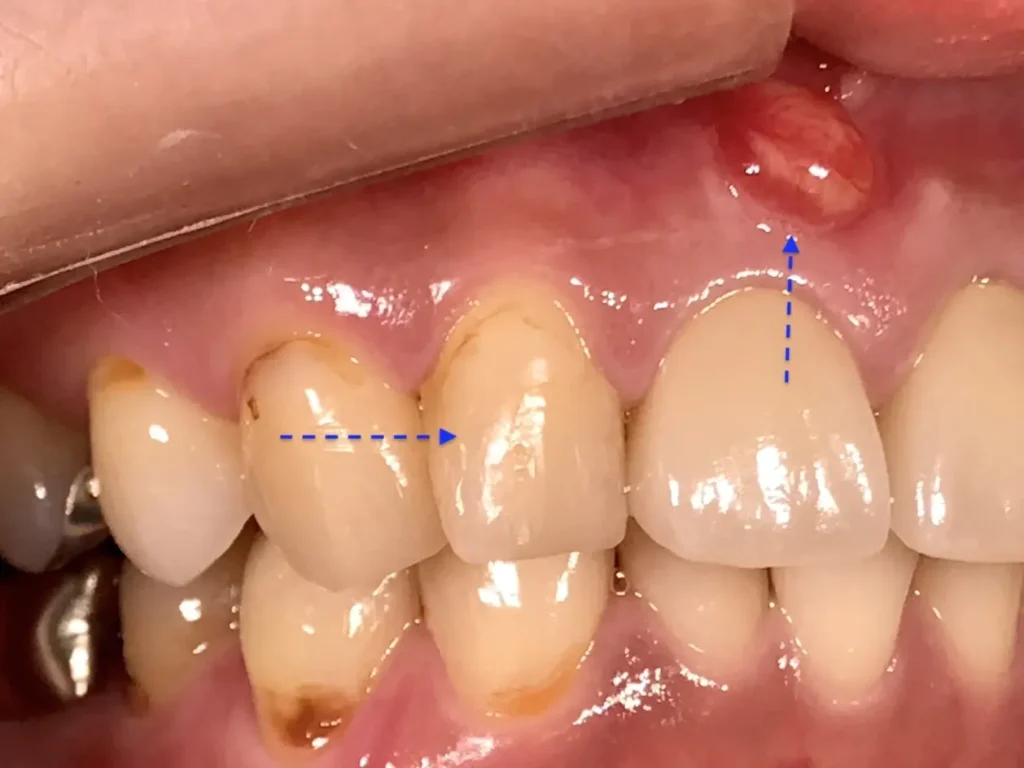

自費根管治療症例4 治療前(外科的歯内療法)

「前歯にニキビみたいなものができた」

初診時

離れていますが真ん中が原因歯です

初診時レントゲン写真

治療はしてありますが、根の先が黒ずんで見えます

CT画像

唇側の顎骨が溶けて穴が空いています